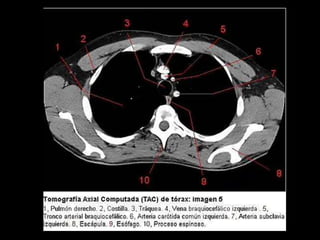

Tac de torax